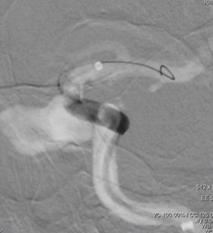

重新行3D造影,根据目标动脉瘤及载瘤动脉选择角度,路图下在0.014 Synchro2微导丝引导下将WILLIS®覆膜支架(4.5*16mm)准确定位至左侧颈内动脉C3动脉瘤位置。

6F Navien导管超选至动脉瘤远端,微导丝引导下WILLIS®支架到位。

球囊首次扩张,支架展开,首次造影图示动脉瘤近端贴壁不良,有造影剂渗漏至动脉瘤腔内,故再次充盈球囊扩张支架近端。

再行造影见动脉瘤不显影,无造影剂渗漏,血管重建满意。